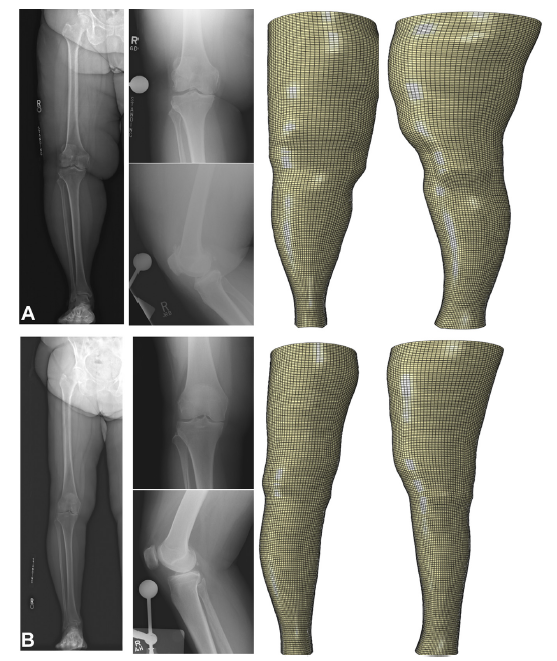

As has been observed by Elkin et al [20], among the 232 obese subjects analyzed, large variations in leg shape were observed. This point is demonstrated in Figure 3, where patient A and patient B both were morbidly obese with BMI > 40 kg/m2. Patient B showed a pattern of more central adipose distribution.

Consistent with Mont's statement, in exploring the relationship between tourniquet time (a surrogate of surgical difficulty) and anthropometric measurements versus tourniquet time and BMI, Armstrong et al [21] reported that tourniquet time was significantly associated with preoperative inferior knee circumference (P = .025) and ankle circumference (P = .003), as well as the intraoperative depth of incision at the quadriceps (P = .014). In contrast, BMI was not significantly associated with tourniquet time.